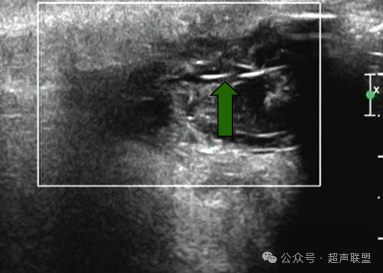

.超声表现

1.紧邻皮下软组织的异常回声,部分可见窦道,窦道开口于皮肤,但是在临床工作中很少能看到窦道;

2.骶尾部中线囊性或囊实性包块

3.与肛管无关

4.壁厚,与椎管不通或通

5.臀部毛发较多

6.混合回声病灶,炎症的不同时期病灶声像图表现多样。多为以无回声为主的混合回声包块,该病是一种慢性炎症性疾病,在炎症的进展过程中部分病例可以出现以实性成份为主的混合回声包块;

7.毛发样强回声是该病的重要特征性表现。该病例声像图内可见线样强回声,为毛发,故诊断为藏毛窦。